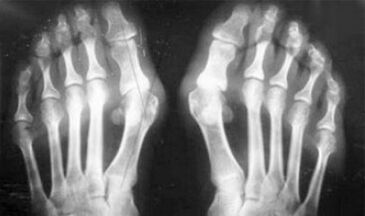

Gördüğünüz gibi, semptomlardaki farklılıklar önemsizdir: her iki durumda da ağrı, sertlik ve yorgunluk vardır. Artrit ve artroz, insan vücudundaki farklı eklemleri etkileyebilir. Omurga ve intervertebral disklere zarar vererek, osteokondroz gelişir - artroza benzer. Hastalığın yerine bağlı olarak, ayak bileği, omuz, kalça eklemleri vb. Arthroz ayırt edilir.